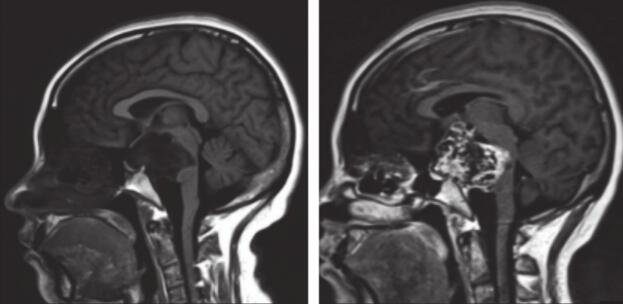

患者于2014年9月15日出现突发头痛伴恶心呕吐,伴双眼复视,就诊外院查头CT诊断蛛网膜下隙出血,当地医院住院对症支持治疗后患者头痛及复视症状消失,患者具体诊疗过程不能回忆。2014年9月16日患者进一步查头颅MRI提示鞍上区占位,T1低信号T2高信号,明显均匀强化,外院建议定期随访。患者于2个月前开始出现右眼睑下垂及行走不稳,就诊我院。头颅MRI提示:鞍上可见异常信号肿块影,T1WI低信号,T2WI高信号,增强后混杂增强信号,CT提示病灶钙化(图1)。回忆本次病程,患者无明显头痛及恶心呕吐,无复视,无四肢活动障碍。

图1 2015-2术前影像学检查

鞍上可见异常信号肿块影,MR T1WI低信号,T2WI高信号,增强后混杂增强信号,CT提示病灶钙化